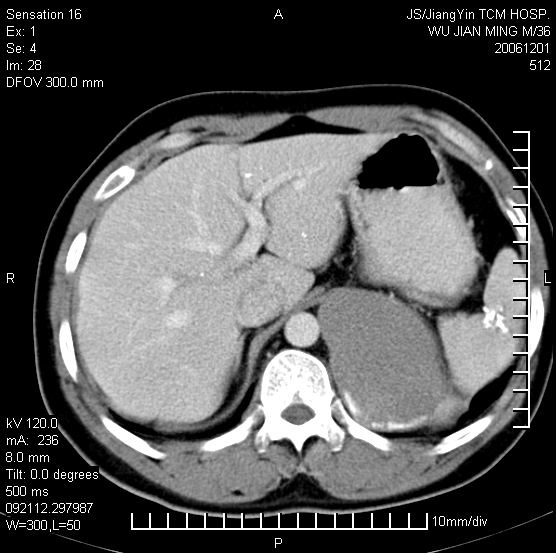

以下是引用dyqct在2006-12-1 21:17:00的发言:[br]左心缘旁及后肋膈窦区见巨大椭圆形混杂密度肿块,周围见大小不等斑片状钙化,内部无强化,周围包膜轻度强化,心脏明显受压变形,即明显占位效应,肿块广基与心包、膈相连。肝、脾内、肝门见多数小结节状钙化影。[br]考虑:1、左心缘旁及后肋膈窦区慢性包裹性胸膜炎(结核性);[br] 2、肝、脾及肝门淋巴结核已钙化。[br]

以下是引用zrs在2006-12-2 17:28:00的发言:[br]肺内、肝脾内虽有钙化,但不支持结核性胸胸膜炎包裹,而支持寄生虫感染![br][br]

以下是引用zyx168在2006-12-2 10:10:00的发言:[br][br]肝脾肺内多发钙化灶